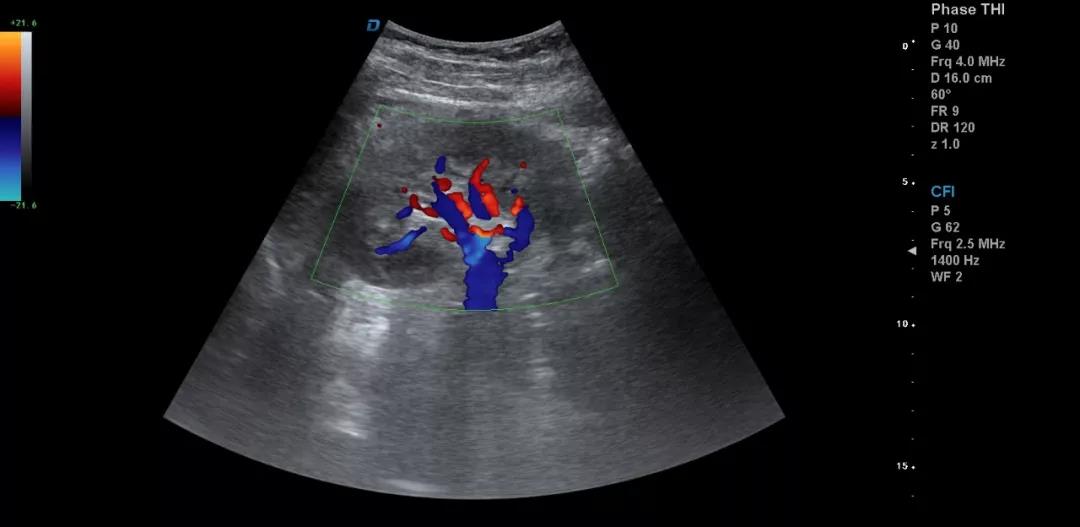

典型圖片、經(jīng)典病例圖片、動態(tài)影像資料積累的多了分析總結(jié)之后就提高了。疑難病例資料積累后,可以隨訪病人,然后總結(jié)得到的臨床資料和病理結(jié)果。

有了手術(shù)結(jié)果和病理才會有真正的提高。按器官、按系統(tǒng)、按學(xué)科進(jìn)行總結(jié)每一個(gè)、每一類疾病正常及異常圖片就是知識的積累。